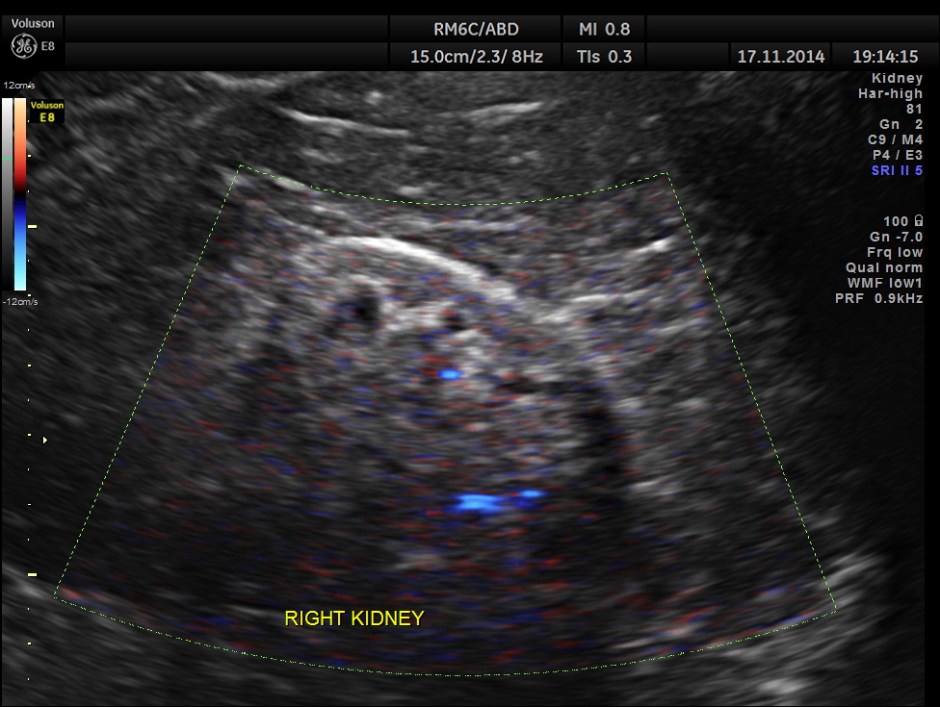

The following pictures show the native kidneys – shrunk with loss of renal architecture , with poor flow seen in Power Doppler.